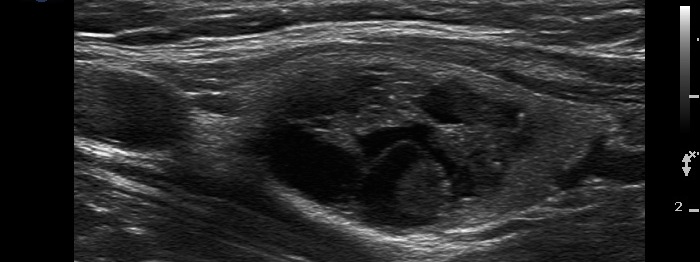

Metastasis of a kidney carcinoma to the thyroid - case 1574 |

Benign hyperplastic nodule (histological diagnosis) - case 1582 |

Both images show one relatively large granule which correspond to punctate echogenic foci.

Parts of the hyperechogenic granules are located in cystic area, while others are found in the solid part of the lesion. The latter might be punctate echogenic foci.